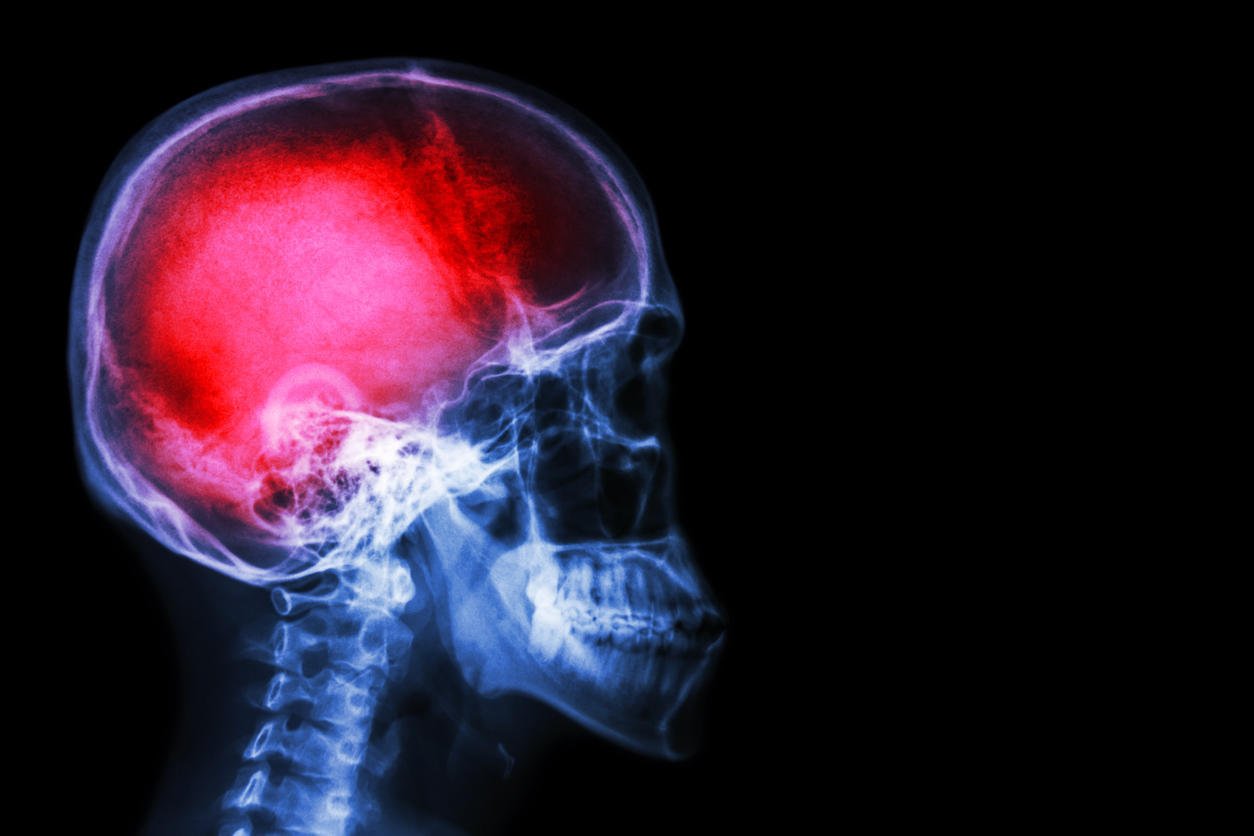

crâne radiologique et rachis cervical (latéral) avec avc

Istock